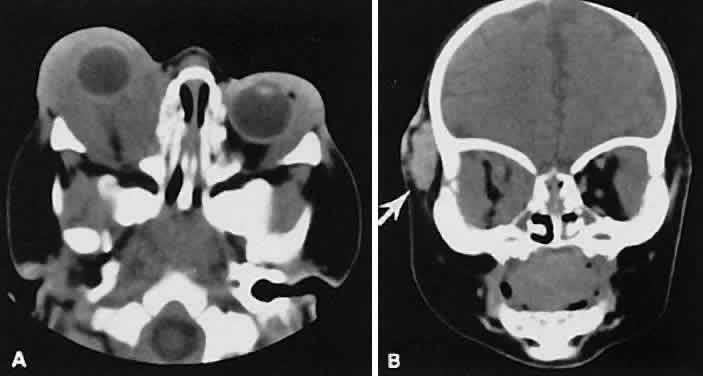

Fig. 5. Axial views of orbital myositis. A. Note increased attenuation with enhancement of the thickened medial rectus and thickened scleral insertion. B. Thickening of the medial rectus muscle along the entire length of muscle is more evident.

Nonspecific inflammatory dacryoadenitis shows enlargement of the lacrimal gland, which typically molds to the shape of the globe (Fig. 6). The adjacent bone is normal, and contrast enhancement of the gland usually is fairly homogeneous. Bilateral involvement may be apparent with certain conditions such as Sjogren's syndrome, sarcoidosis, lymphoma, or even Graves' orbitopathy, although enlarged EOM in the latter condition might make this a more obvious diagnosis.

Fig. 6. Nonspecific inflammatory dacryoadenitis. An isodense enlargement of the lacrimal gland is noted on axial (A) and coronal (B) views. Note the similarity to Figure 18.